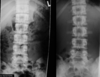

What is the diagnosis? What is the mechanism of injury?

Acute compression fracture (wedge shape) L2 Hyperflexion and/or axial load

42

Which hallmark signs of acute compression fracture are seen here?

* Step defect * Zone of impaction | wedge shaped compression ## Footnote paraspinal edema is another possible sign

43

Is this injury stable or unstable? What is the appropriate follow-up?

Stable injury (1 column of Denis affected) Orthopedic referral | acute compression fracture L2